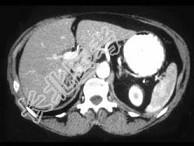

- 单项选择题女,35岁, 无意中发现血压高,实验室检查: 血和尿中醛固酮水平增高,请结合所提供图像, 作出诊断 ( )

A、右肾上腺增生

B、右肾上腺Cushing腺瘤

C、右肾上腺皮质腺瘤

D、右肾上腺转移瘤

E、右肾上腺囊肿